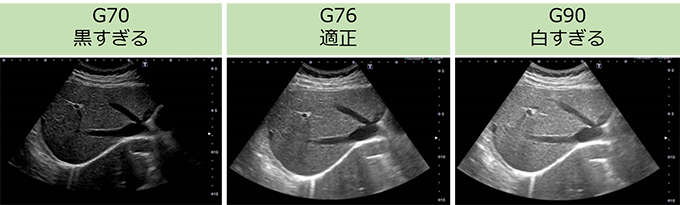

(1)ゲイン

ゲイン(図8)は、画面全体の明るさを調整するもので、低すぎると画面全体が暗く、高すぎると画面全体が明るくなります。適切な調整が必要になります。

図8 ゲイン